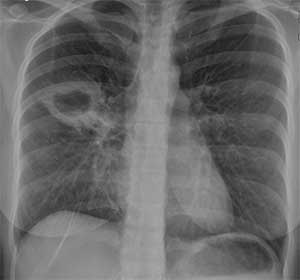

Nampula (IKWELI) – Na província de Nampula, a mais populosa do país, 240 pessoas, em 100 mil habitantes, vivem com a tuberculose, uma doença que nos últimos 9 meses do corrente ano fez 88 óbitos.

As principais vítimas são jovens, maioritariamente do sexo masculino.

Nilton Napoleão, supervisor provincial da Tuberculose, refere que os números são preocupantes, aliado com a desistência no tratamento.

“Olhando aquilo que são os casos de tuberculose de todas as formas, nós reduzimos por causa das actividades de sensibilização que temos tido ao nível das comunidades,” disse a nossa fonte, revelando alguma preocupação com a tuberculose infantil, pois no período em referência foram registados 473 casos, contra 191 do igual período comparativo.”

Na província, os distritos de Nampula, Mogovolas e Eráti são os que mais casos registam. (Virgínia Emília)